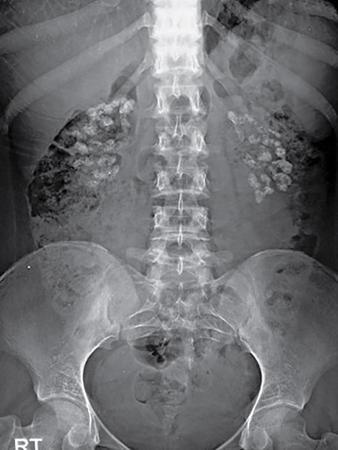

Normal hepatic and splenic soft tissue density can be appreciated in both upper quadrants. The properitoneal fat strip can be seen in bilateral paracolic gutters and the psoas and renal shadows can also be appreciated (Fig. 10.6.1).

Image

Fig. 10.6.1 Normal plain scout image showing soft tissue density outlines of liver (L), spleen (S), kidneys (R) and psoas shadow (dotted line).